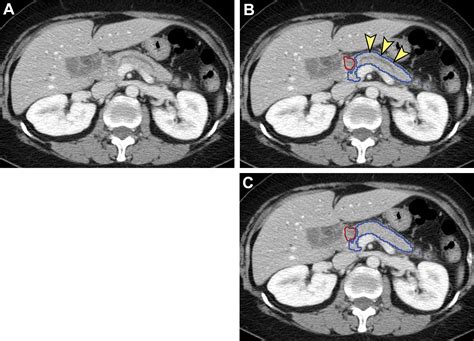

Interpreting CT Scan Results

After the Pancreatic Adenocarcinoma CT Scan, a radiologist will review the images to look for any signs of pancreatic adenocarcinoma. The results will be sent to the referring physician, who will discuss them with the patient. The scan results can provide valuable information, including:

• The presence and location of any tumors.

• The size and shape of the tumor.

• Whether the tumor has spread to nearby organs or lymph nodes.

• Any other abnormalities in the pancreas or surrounding tissues.

If a tumor is detected, further tests such as a biopsy may be recommended to confirm the diagnosis and determine the type of cancer. The biopsy involves taking a small sample of tissue from the tumor for laboratory analysis.

These advanced imaging techniques can complement the information provided by a Pancreatic Adenocarcinoma CT Scan, helping to create a comprehensive picture of the cancer's extent and characteristics.